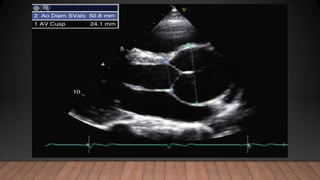

• Following diagnosis of MFS, an echocardiogram is recommended at 6

months to assess the progression of aortic disease

• If measurements remain stable, echocardiographic follow-up can be

performed every 6 months in children and on an annual basis in Adults.

• Baseline echocardiographic imaging requires diameter measurement at the

level of the sinuses of Valsalva and should be indexed to age and body

surface area